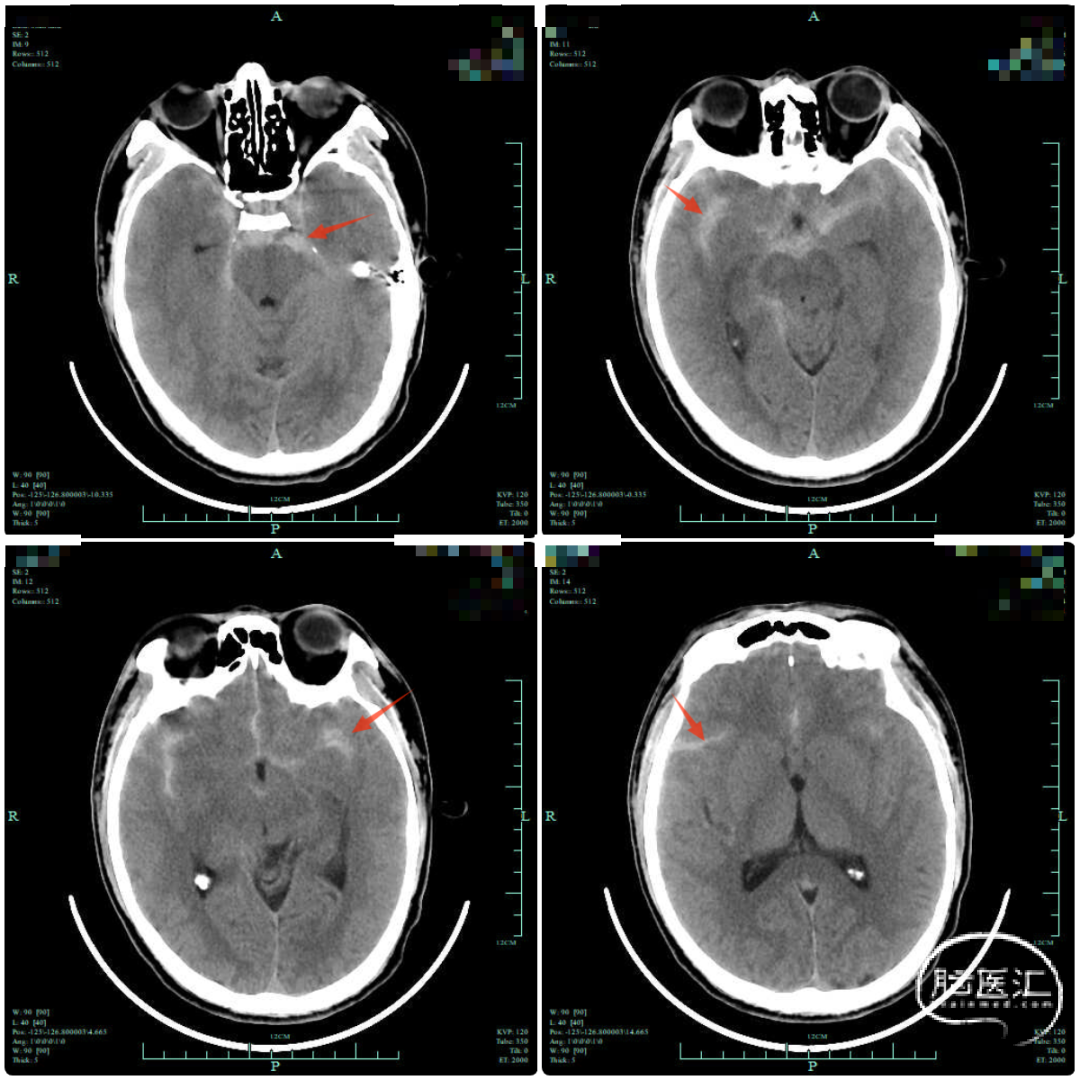

辅助检查

1. 右侧A1近端动脉瘤破裂伴蛛网膜下腔出血明确,该部位动脉瘤发病率低,目前检查首先考虑为真性动脉瘤,治疗可选择血管内介入治疗,也可选择开颅夹闭动脉瘤。

2. 该部位动脉瘤介入在微导管超选中难度系数高,对微导管塑形要求高,且术中微导管稳定性差,易踢管。

3. 若选择开颅夹闭,动脉瘤藏于额叶后方,需将侧裂彻底分离,进行阻断后夹闭,需注意细小分支避免损伤。经与患者及家属充分沟通后,患者要求行开颅手术夹闭治疗。